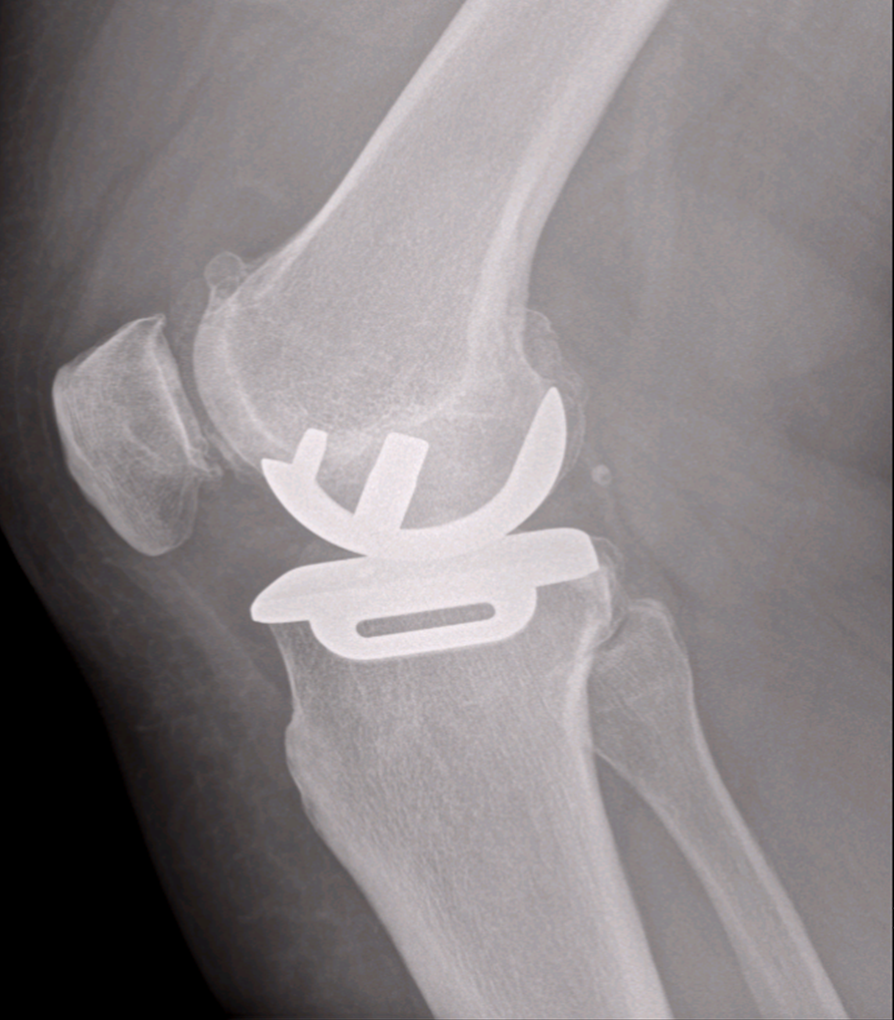

Post-operative Total Knee Replacement X-Ray

Post-operative X-Ray Total Knee Replacement Surgery

Total Knee Replacement

Total knee replacement surgery can be performed in painful arthritic knees that are no longer helped with non-surgical treatments. Total knee replacement is carried out to treat arthritis in any area of the joint – especially if more than one area of the knee is arthritic. The surgery removes the surface of the joint – replacing it with metal and plastic. In some circumstances the back part of the patella may also be resurfaced with plastic.